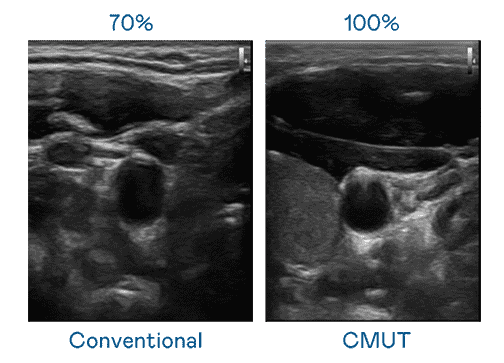

CMUT 技术是一种用电容式微机电元件来产生超音波讯号的技术。。与传统 PZT 压电式技术相比,,,,CMUT 频宽增加 30%,,,,更宽频的超音波讯号让影像解析度大幅提升,,,,是实现高影像品质医疗超音波扫描、、、促进精准医疗发展的关键技术。。

大频宽带来超清晰影像

超音波影像的解析度高低,,,,首先取决于探头能发出的讯号频宽。。。。糖果派对 CMUT 可提供高清晰的超音波讯号,,,提供高频宽、、高灵敏度、、、、影像纹理细节更高的超音波影像,,协助医护人员缩短影像判读时间及利用精准的医疗影像进行诊断。。。。